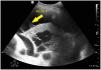

A 52-year-old patient with a history of acquired immunodeficiency syndrome (AIDS) was admitted to our Unit due to Streptococcus pneumoniae community-acquired pneumonia. The chest radiographs evidenced right basal infiltration, and the computed tomography (CT) study showed necrotizing pneumonia with a probable incipient lung abscess. The clinical course was poor, with hypoxemia refractory to cycles in prone decubitus. Pulmonary ultrasound revealed pleural effusion containing hyperechogenic fibrous tracts (plankton sign) (Fig. 1, arrow 1), right basal infiltration with hyperechogenic parenchyma secondary to hepatization, air bronchogram (Fig. 2, arrow 2), and well delimited internal hypoechogenic trabeculate zones consistent with necrotizing pneumonia and lung abscess (Fig. 2, arrow 3).